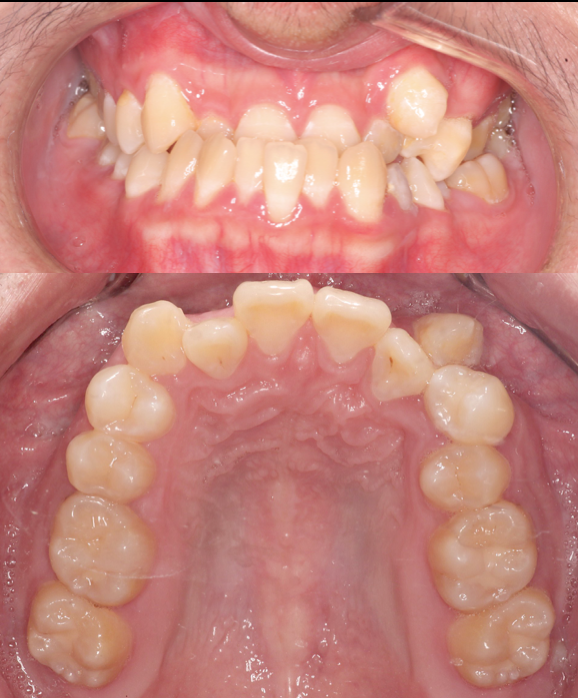

Before

After

Braces- Molar Closing

Orthodontic treatment was performed to align crowded teeth and close lower molar spaces bilaterally. On the left side, space was closed by mesializing the wisdom tooth and distalizing the second molar. On the right side, protraction of the second and third molars was done to close the edentulous space. Treatment completed by the orthodontic team at Moral Dental Clinic.